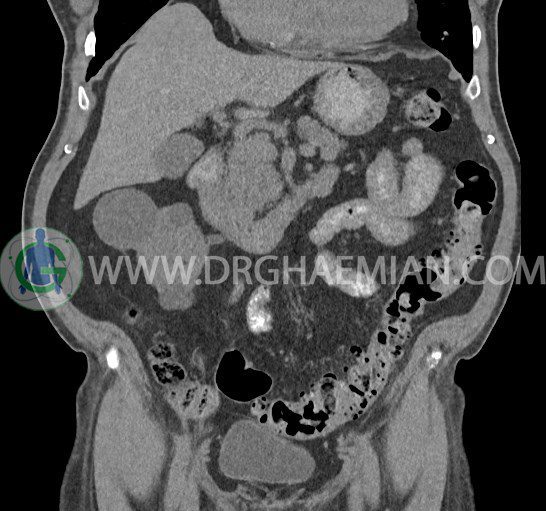

سی تی اسکن لگن یکی از روش های تصویربرداری با سی تی اسکن است. این روش با استفاده از تشعشعات تصاویر عرضی از ناحیه شکمی ایجاد میکند. در این کیس ديورتيكولوزيس، کیست های کورتیکال در هر دو کلیه، لنفادنوپاتی، کلسیفیکاسیون دیواره آئورت و شریان ایلیاک، تغییرات DJD ناحیه توراکولومبار و پروستات بزرگتر از عادی دیده می شود.

در سي تي اسکن اسپيرال شکم و لگن با و بدون کنتراست خوراکی و وريدی (مولتي ديدکتور 16 با مقاطع ظريف و بازسازي هاي ساژيتال و کرونال):

– ديورتيكولوزيس در کولون نزولي وسيگموئيد

لنفادنوپاتي به ابعاد mm 22 x 25 مجاور شريان ايلياک خارجي چپ و به ابعاد mm 17 x 28 مجاور شريان ايلياک خارجي راست